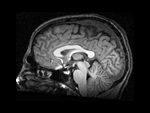

SAGITTAL MRI